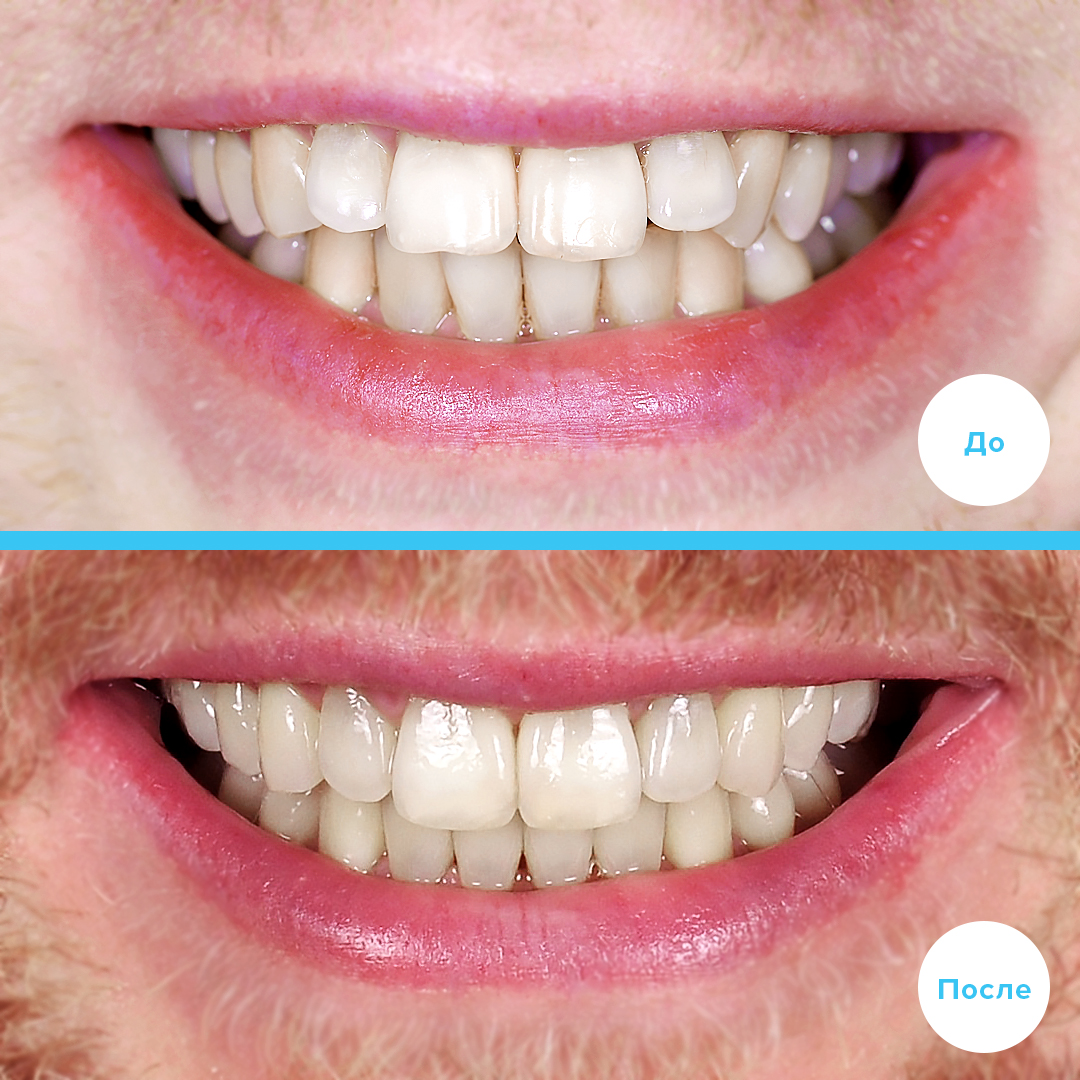

ЛЕЧЕНИЕ ДИСТАЛЬНОГО ОТКРЫТОГО ПРИКУСА С УДАЛЕНИЕМ

Провели лечение дистального открытого прикуса с удалением зубов и установкой самолигирующих брекетов Damon Clear/Q.

Пациенту 34 года

Срок лечения: 3 года